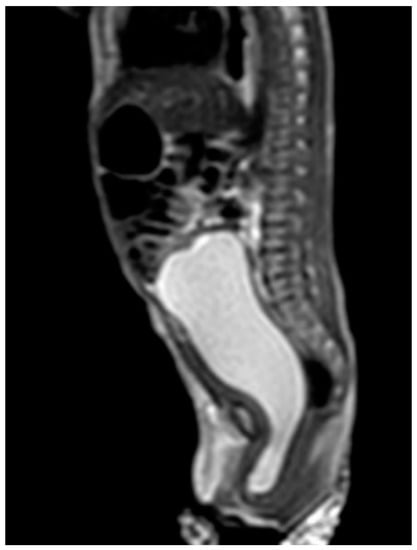

Case 3 was a female infant born at 34 weeks of gestation. The antenatal ultrasound showed fetal ureteral obstruction and oligohydramnios. She had a poorly developed vestibule with a small orifice near the clitoris and high-type imperforate anus, indicating cloacal malformation. A double-barrel colostomy and drainage of 30 mL turbid urine of the orifice of the common channel, possibly from the distended vagina, was performed at 5 hours of age. Abdominal ultrasound at 1 day of age showed a 7.5 cm cystic mass in the lower abdomen, but it decreased in size on the next day. Water instillation via urinary catheter visualized the urinary bladder and enlarged the cystic mass on real-time ultrasound, suggesting HMC with vesicovaginal fistula. The patient received spinal lipoma excision at 8 months of age for the lipomyelomeningocele, and repair for tetralogy of Fallot at 1 year of age. Posterior sagittal anorectovaginourethroplasty using the Pena method was performed at 1 year, 8 months of age, and the distal vagina was replaced by a 5 cm length of rectum. She began menstruating at 12 years, 10 months, which was associated with cyclic abdominal pain, and the MRI detected uterine didelphys with left hematometrocolpos, hemivagina, and left renal agenesis (Figure 4 and Figure 5). Hysteroscopy was performed via the neovagina, and one bulging mass in the left side was observed. The right uterus cavity was normal with smooth endometrium. Herlyn–Werner–Wunderlich syndrome was diagnosed. The patient anticipates left hemi-hysterectomy and transcervical resection of the vaginal septum.

Figure 4.

MRI of case 3: hematometrocolpos (asterisk) and uterine didelphy (arrow and arrowhead).